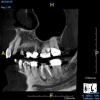

(10.) Tooth No. 31 in this 14-year-old patient does not exhibit caries. It is a “ghost tooth.” The lack of a periapical pathosis, the location of the tooth relative to the inferior alveolar nerve, and the development of tooth No. 32 are all visible in the CBCT image. These factors will aid the clinicians in developing a treatment plan to deal with this unusual internal resorption case.

Figure 10